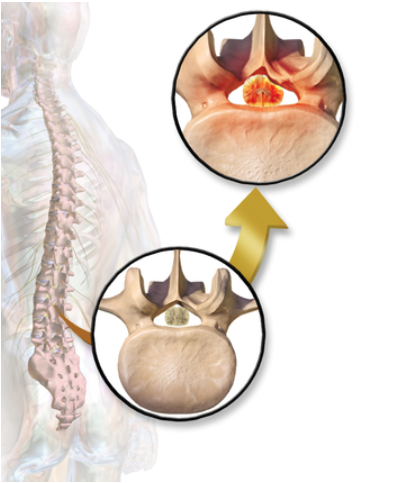

Typically, spinal stenosis is a condition that progresses over time. However, traumatic incidents to the low back can cause additional displacement to the vertebra of the spine (image 3). When this happens, the displaced vertebra can begin to compress onto the spinal cord and nerves. This abnormality can cause symptoms such as pain with prolonged standing, traveling pain down the leg(s) and relief when sitting.

Image 3. Visual representation of lumbar spinal stenosis. Source.